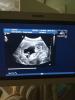

Вообщем была сегодня на скрининге,и я так рада что с ребеночком всё хорошо. По узи всё в норме ктр 68мм. и сердечко бьётся 156 уд.мин.

На УЗИ срок день в день поставили как по последним месячным 12.6😍и ещё сказали скорее всего девочка❤️я счастлива😭фото принцессы прилагается в комментах 🌸👑

Такая большая уже кажется на узи

@o.d.majorova спасибо, да кажется большая, а в сантиметрах ещё даже 7 см нет, я такая сейчас счастливая, слов нет❤️😍